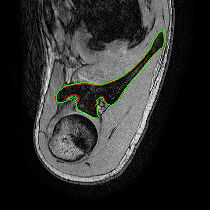

Refer to captionRefer to captionRefer to captionRefer to captionRefer to captionRefer to captionRefer to captionRefer to captionRefer to captionRefer to captionRefer to captionRefer to captionRefer to captionRefer to captionRefer to captionRefer to captionRefer to captionRefer to captionRefer to captionRefer to captionRefer to captionRefer to captionRefer to captionRefer to captionRefer to captionRefer to captionRefer to captionRefer to captionRefer to captionRefer to captionRefer to captionRefer to captionRefer to captionRefer to captionRefer to captionRefer to captionRefer to captionRefer to captionRefer to captionRefer to captionRefer to captionRefer to captionRefer to captionRefer to captionRefer to captionRefer to captionRefer to captionRefer to captionRefer to captionRefer to captionRefer to captionRefer to captionRefer to captionRefer to captionRefer to captionRefer to captionRefer to captionRefer to captionRefer to captionRefer to captionRefer to captionRefer to captionRefer to captionRefer to captionRefer to captionRefer to captionRefer to captionRefer to captionRefer to captionRefer to captionRefer to captionRefer to captionUNetCAE-UNetcGAN-UNetProposed method

Fig. 3: Automatic pathological segmentation of scapula using UNet [1], CAE-UNet [5], cGAN-UNet [8] and proposed method. Groundtruth and estimated delineations are in red and green respectively. In the first comparison, UNet under-segments the bone area, whereas other approaches achieve more accurate scapula delineations. In the second example, the proposed method captures more complex bone shape and subtle contours compared to other architectures.